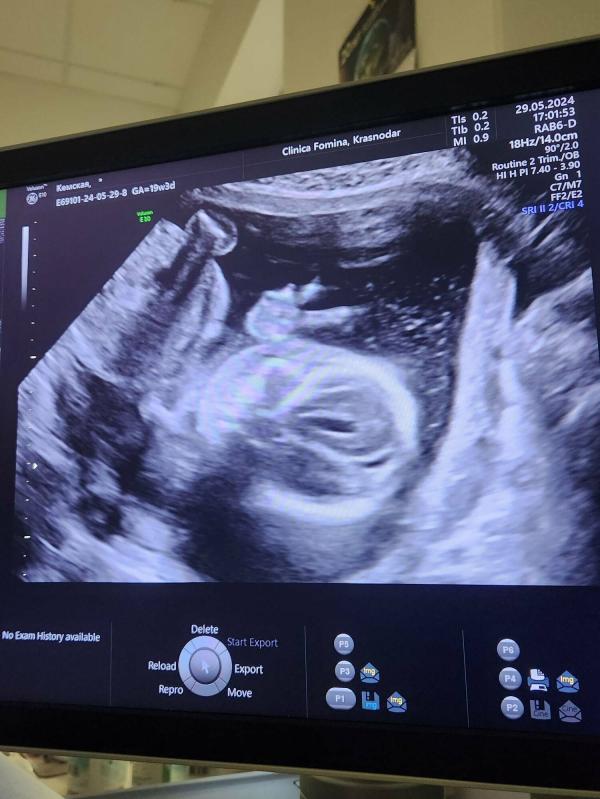

Всем привет. Прошла сегодня 2 скрининг. Все хорошо, но признаки низкой плаценты. Сказали, возможно у вас поднимется.

Зато человек показал нам ✌️